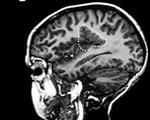

• МРТ головного мозга. Нейровизуализация - основной способ подтвердить диагноз микрогирии. По результатам МРТ определяется уменьшение размеров корковых извилин в области сильвиевой борозды или других участках головного мозга, также могут быть трещины или кисты вещества головного мозга, участки нарушения кровотока, участки некроза или ишемии.